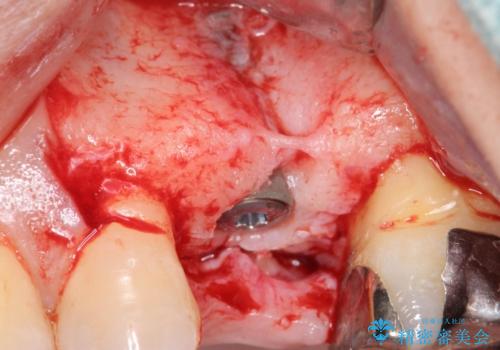

歯茎が腫れる インプラントでの治療

- 40代女性

- 10ヶ月

- 5-10回

- 左上5/インプラント:242,000円 骨増生:55,000円 カスタムアバットメント:110,000円 インプラント用仮歯:22,000円 ジルコニアクラウン:121,000円 合計550,000円費用は治療当時の料金となります

- 外科手術のため、術後に痛みや腫れ、違和感を伴います